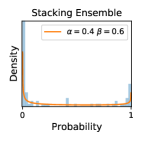

To model how different classifiers will respond to a given input , we assume that the prediction from classifier is sampled from a beta distribution that is characterized by two parameters by and . We further assume that is fixed to the same constant value for all ’s. Under this assumption, each input can be described by ( can be calculated since is fixed), easing further analysis. The Severity Level (SL) of the case represented by image can be characterized by the parameter . The larger the value of , the more severe the case of is. When and are close, the case is ambiguous as the distribution shifts towards being symmetric (i.e. signifying much disagreement among classifiers) rather than being one-sided (i.e. consensus among classifiers that is negative or positive). We provide a set of examples in Figure 2 and also Figure S.8 in the supplementary materials showing how the beta distribution can be used to capture diverse predictions given by an ensemble learner.

We conducted a case study on diagnosing diabetic retinopathy with ensembles of DL models. For benchmarking the performance of our ensemble-based solutions under the scheme described in Sec.3.3, we used two popular collections of diabetic retinopathy image data, the Kaggle Diabetic Retinopathy dataset [22] (hereafter referred to as “Kaggle-DR”) and the Messidor-2 dataset [23], each respectively consisting of and high resolution images. Diabetic retinopathy is graded into five SLs, as displayed in Figure 2. Following the problem setup used in previous papers [24], we trained models to distinguish the referable (SL2-4) cases from the non-referable ones (SL0 & SL1) (see Section B.1 for more detailed descriptions). We also tested our trained ensemble models on two o.o.d. image datasets (ImageNet [25] and CIFAR-10 [26]) to examine their capabilities of identifying o.o.d. inputs (see Section B in the supplementary materials).

In contrast, the MC-dropout method showed the worst overall performance among the three, as it can be seen from the high ratios of SL0 examples among the uncertain negatives in Figure 4. The histograms in Figure 2 provides another perspective to look into the phenomenon, where a decent proportion of MC-dropout model’s predictions on SL0 inputs entailed low confidence (far from 0 or 1), which from another angle explained why MC-dropout was less specific in terms of lower FNP; many no-DR inputs (i.e. SL0) were erroneously assigned high uncertainty by MC-dropout models.

It is still an open question why the evaluated MC-dropout networks signaled relatively high uncertainty on SL0 & SL3 & SL4 data that are less likely to be ambiguous. We conjecture that much of the “uncertainty” indicated by disagreement among test-time dropout samples actually reflects the stochastic nature of dropout networks rather than the real decision uncertainty associated with the data. It is worth noting that the MC-dropout model we evaluated was not weak per se; they all achieved above Area Under Curve (AUC) scores on test sets. The weakness of individual test-time samples (which explains their low-confidence predictions on SL0 & SL3 & SL4) might have been hidden when they are aggregated into an ensemble—a well-known advantage of ensemble learning. Our results suggested that the uncertainty information given by implicit ensemble methods such as MC-dropout and TTA might not be as reliable as that from explicit ensemble approaches (e.g., stacking ensembles). Similar findings on MC-dropout can be found in some previous papers [1].